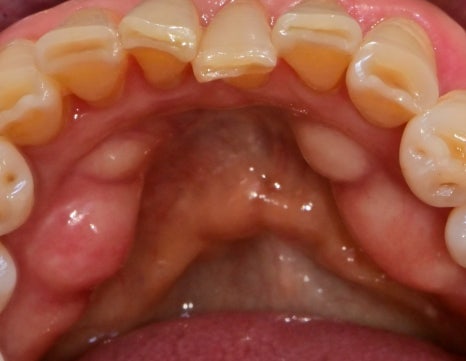

일반적으로 아래턱 앞니 안쪽은

침샘과 가깝고, 칫솔질의 각도가 용이하지 않기 때문에

치석이 잘 쌓이는 환경입니다.

사진과 같이 치석이 쌓이며